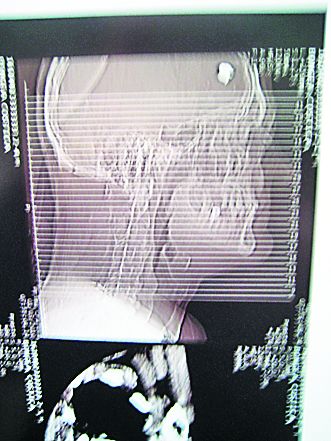

Un poliţist din Brastavăţu, judeţul Olt, trăieşte după ce, zilele trecute, s-a împuşcat de trei ori în cap.

Din spusele medicilor, primul glonţ a ieşit prin mandibulă, al doilea pe sub un ochi, iar al treilea a rămas în creierul bărbatului, care este acum în stare gravă.

Poliţiştul a recurs la acest gest după ce a lovit cu maşina două persoane.